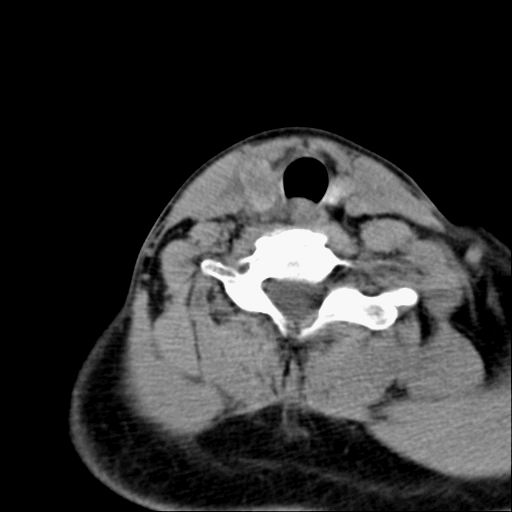

标题: CT23947 右颈部触及00.5x1.5cm质硬长形肿块,疼痛 [打印本页]

标题: CT23947 右颈部触及00.5x1.5cm质硬长形肿块,疼痛

右侧甲状腺腺瘤考虑

甲状腺癌可疑

右侧甲状腺病灶,建议增强或结合b超检查。

右甲状腺占位,建议增强。

甲状腺腺瘤或癌

甲状腺占位  定性有时很难 但无论癌还是腺瘤 还是手术比较好!以下是甲状腺占位的ct鉴别诊断

ct表现:形态不规则的软组织密度肿块,可累及部分或大部分甲状腺组织,密度不均,可坏死、囊变、钙化,增强病灶呈不均匀强化,有局部侵犯或转移时可有颈部淋巴结肿大。

ct表现肿瘤呈稍低密度结节状肿块,边缘光整、锐利病灶均匀强化,少数腺瘤可有钙化。

甲状腺右侧叶占位,定性困难,建议增强。

右侧甲状腺低密度病灶,性质待定;建议行进一步检查。